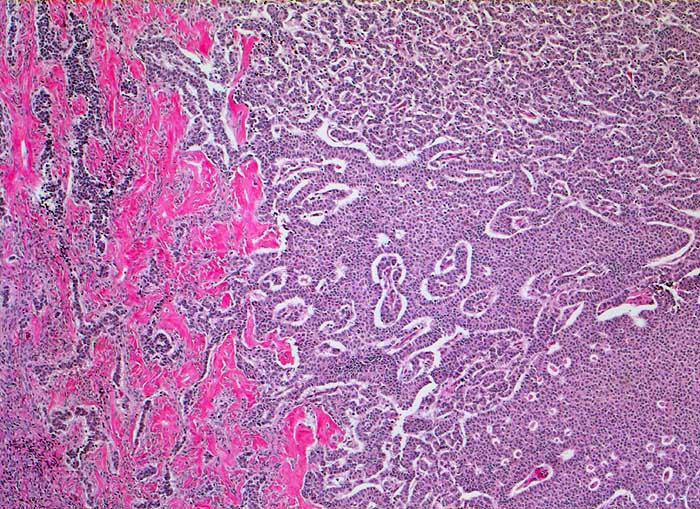

AP/ Granulosazelltumor des Ovars

Granulosazelltumor des Ovars

Ovar

Morphologie

Pathologischer Befund

Normalbefund